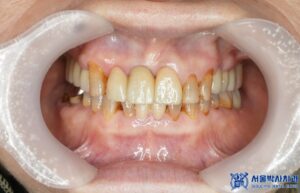

그래서 보존이 가능했던 앞니들과 어금니는

신경치료 후 지르코니아 크라운으로 씌워

튼튼하고 자연스러운 치아로 복원하였습니다.

치료 마무리 후 사진입니다.

환자분께서는 원래 다른 치과를 다니고 계시다가,

그 쪽에서 신경치료한 치아가 너무 아파서

중앙동치과 서울박사치과에 오게 되었는데

신경치료부터 임플란트 수술까지

하나도 아프지 않았다며 매우 만족해 하셨습니다.

또한 불편했던 상악 부분틀니 대신

임플란트를 식립한 후,

틀니로 인한 잇몸 통증에서

완전히 해방되어 너무 좋다고 하셨습니다.